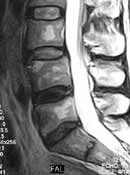

Грыжа по типу экструзии возникает при пенетрации грыжевого фрагмента через разрыв наружных волокон фиброзного кольца (Рис. 4). Во всех случаях, независимо от степени эструзии остается связь между грыжевым фрагментом и центральным субстратом диска.

Рис. 4. Грыжа по типу экструзии (пролабс).

Грыжевое выпячивание распространяется выше и ниже межпозвонкового пространства от нескольких миллиметров до полутора сантиметров, что отчетливо видно на сагитальных сканнах по Т2W, как зона с низким сигналом на фоне яркого сигнала дурального мешка. При этом отмечается компрессия дурального пространства и можно увидеть усиленный МР-сигнал выше и ниже грыжи.